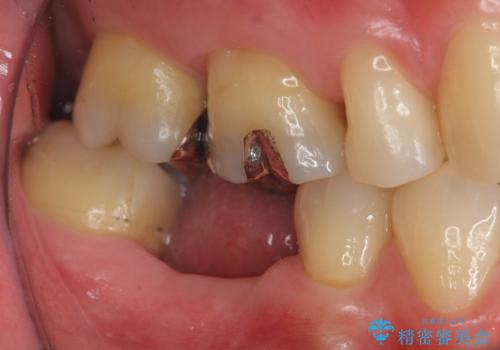

- 歯の破折により失ってしまった右下の歯の機能回復を求めて来院されました。

取り外しの必要な入れ歯や、歯を大きく削る必要のあるブリッジではなく、インプラント治療を希望されました。

骨の増成を含むインプラント治療を計画します。